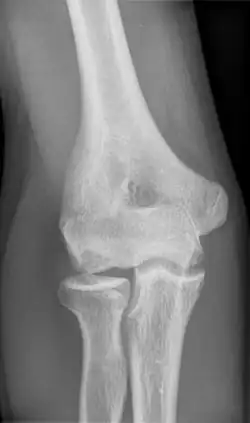

| Morbus Panner Osteonecrosis in condylus radialis humeri |

Panner disease is an osteochondrosis of the capitellum of the elbow.[1] Panner disease is primarily seen in boys between the ages of five and ten years old.[2] Panner disease is often caused by excessive throwing due to valgus stress. The disease causes pain and stiffness in the affected elbow and may limit extension; the affected elbow is usually on the dominant arm the child uses.[3] The disease may be associated with pitching and athletic activity. On radiographs, the capitellum may appear irregular with areas of radiolucency. Treatment is symptomatic, with a good prognosis. Treatment is minimal and includes restricting athletic activity to allow for the elbow to heal and for pain to be relieved.[4] The disease is named after the Danish radiologist Hans Jessen Panner (1871–1930).

To confirm the diagnosis, an x-ray or MRI scan will be done. The radiograph will enable the doctor to visualize irregularities and see the shape of the capitellum and also visualize the growth plate. In Panner Disease, the capitellum may appear flat and the bone growth plate will look irregular and fragmented. The areas where bone breakdown has occurred can also be visualized on the radiograph.[2] When the patient undergoes an MRI scan any irregularities of the capitellum will be able to be visualized, and the bone will be able to be visualized in more detail to determine the extent of swelling, if any. In the MRI results for Panner disease, there will be a decreased signal intensity of the capitellum on a T1 series and increased signal intensity on a T2 series.[2][5]

Although the exact cause of Panner Disease is unknown, in recent research, it has been concluded that it may be associated with frequent throwing or other athletic activity.[4] In the same article that talks about varying osteochondrosis diseases, it is pointed out that Panner Disease always involves alteration of the capitellum, which can be visualized by radiography. In another research article, the research team aimed to summarize the best available evidence for diagnosis and treatment for Panner Disease. In the article it was found that the most common symptoms that patients with Panner Disease present with are elbow stiffness and swelling, limited range of motion, and limited elbow extension.[2] In alignment with the previously mentioned article, the team of researchers also concluded that Panner Disease involves irregularity of the capitellum, specifically that it appears flattened. Panner Disease often gets misdiagnosed as osteochondritis dissecans (OCD), and in this article they distinguish the difference between the two diseases are age difference and radiographic findings.[2] In alignment with the two previously discussed articles, another article that reports on three case studies of Panner Disease, states that the primary treatment that is used for Panner Disease is rest and restriction from all physical and athletic activity that involves the use of the upper extremities; the activity is suggested to be ceased until the symptoms are relieved.[5]